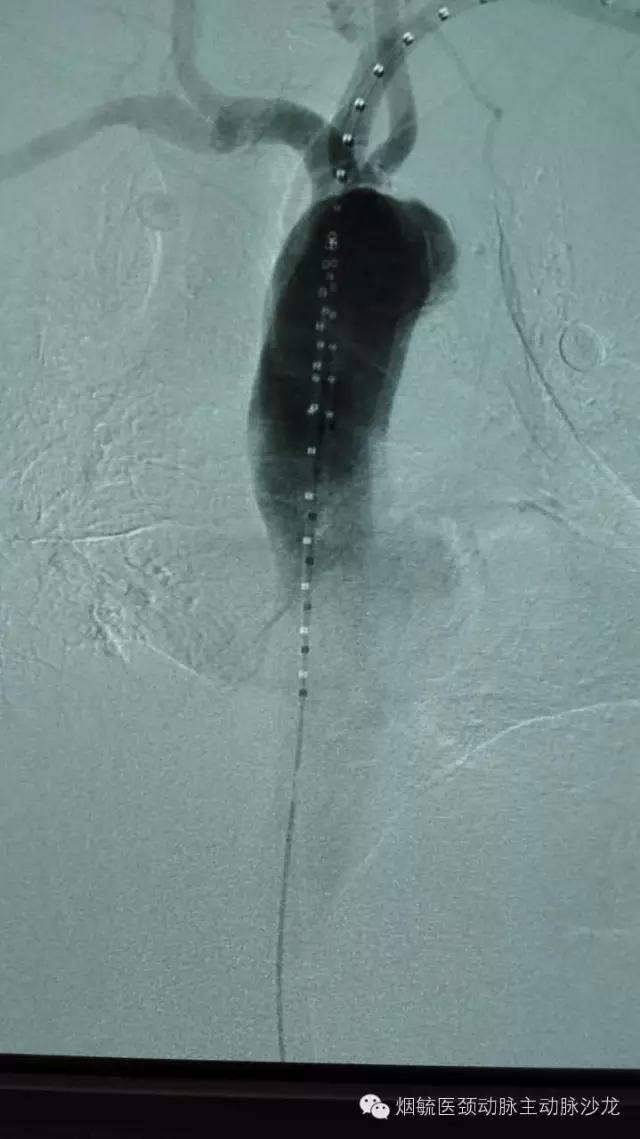

3天前60岁的王大爷前突然胸背部剧烈疼痛,疼到大汗淋漓,只能弯腰或屈膝卧床来缓解疼痛。在外院检查出胸主动脉穿透性溃疡合并璧间血肿,属于濒临破裂穿孔形成假性动脉瘤,必须立即手术,由于外院条件限制,家人带着王大爷来到烟台毓璜顶医院血管外科就诊。接诊的勇俊副主任医师为王大爷进行了紧急控制血压止痛等对症处理,并迅速组织科室专家会诊,讨论病情,制定手术方案,以杨牟教授为首的专家团队一致认为,手术刻不容缓,需紧急处理。在麻醉科及导管室工作人员的配合下,由张居文副主任医师带领的勇俊副主任医师、刘国龙主治医师和王涛住院医师组成血管外科动脉小组当天为患者实施了“胸主动脉腔内隔绝术+左锁骨下动脉烟囱置放手术”,手术顺利,患者转危为安。